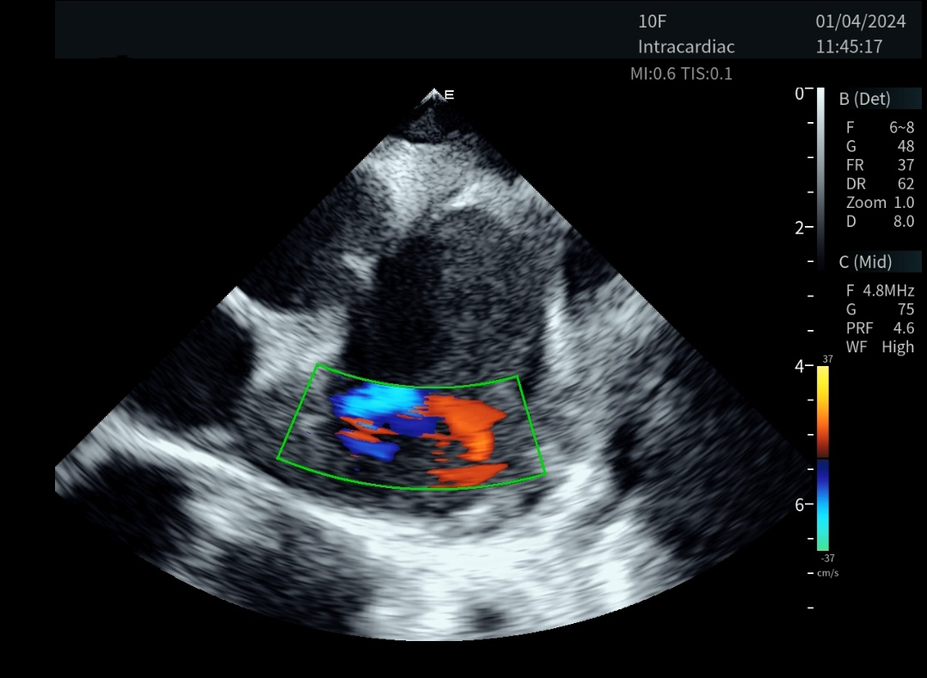

Figure 2

The novel ICE catheter recorded color doppler ultrasound images of the left atrial appendage.